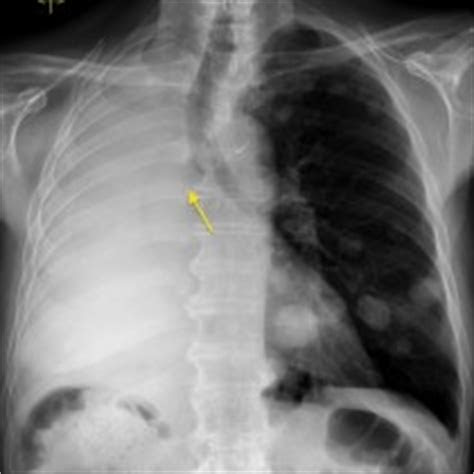

The 38-year-old woman went to the emergency room after she experienced shortness of breath and a sharp pain in her chest, according to the report, published Jan. 22 in The Journal of Emergency Medicine. She said her symptoms had started suddenly that day and seemed to be getting worse.

Five weeks earlier, the woman had developed symptoms of COVID-19, including fever and muscle aches, and had tested positive for the novel coronavirus. At that time, she had been able to treat her symptoms at home with acetaminophen and an inhaler. She had gone through an initial recovery period from her illness, but then her new symptoms started.

An X-ray at the ER showed she had “bilateral pneumothorax,” meaning both of her lungs had collapsed. A collapsed lung (pneumothorax) occurs when air leaks from the lung into the space between the lung and the chest wall, which puts pressure on the lung and prevents it from expanding properly, according to the National Institutes of Health.